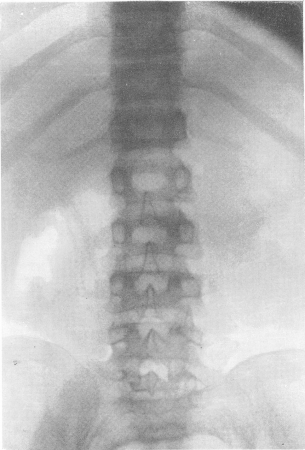

Fig. 279. Același pacient Osteocondrodystrofia. Schimbările caracteristice ale coloanei vertebrale sunt brachypondylia sistemică.

Pe roentgenogramele scheletului toracelui, forma prismatică atrage atenția, sternul cu capătul inferior este proeminent în față, clavicula este ridicată. Coastele sunt îngroșate, foarte largi și plate. Acestea sunt împinse puternic, adică spațiile intercostale sunt înguste. Organele diafragmei și subdiafragmei sunt deplasate în sus, în direcția craniană. În ceea ce privește coloana vertebrală, imaginea radiografică patologică este deosebit de pronunțată și constantă (figurile 279 și 280). Toate fără excepție, corpul vertebrelor are o înălțime redusă, aplatizată, adică există o brachypondylia sistemică. Din nefericire, adesea se spune și se scrie despre platipondilie, ceea ce înseamnă nu numai o scădere a înălțimii corpului, ci și o creștere reală și nu aparentă a dimensiunilor transversale ale corpului vertebral. Adevărata și, în plus, o scurtare semnificativă a întregii coloane coloanei vertebrale are loc în detrimentul părții osoase a acesteia, - discurile cartilaginoase intervertebrale nu reprezintă o schimbare specială. Procesele articulare, precum și procesele transversale și spinoase, sunt scurte și ciudate.